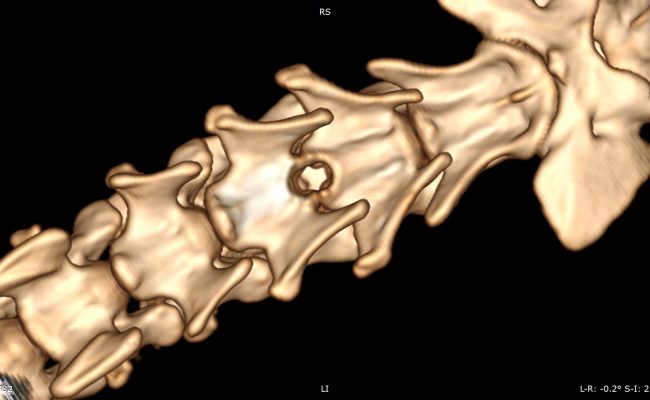

2025-12-31_125154

2025-12-31_125327

Hernie thoracolombaire sur un Teckel.

À gauche, reconstruction scanner multiplanaire mettant en évidence une hernie discale T13–L1 latéralisée à gauche, responsable d’une compression focale de la moelle épinière.